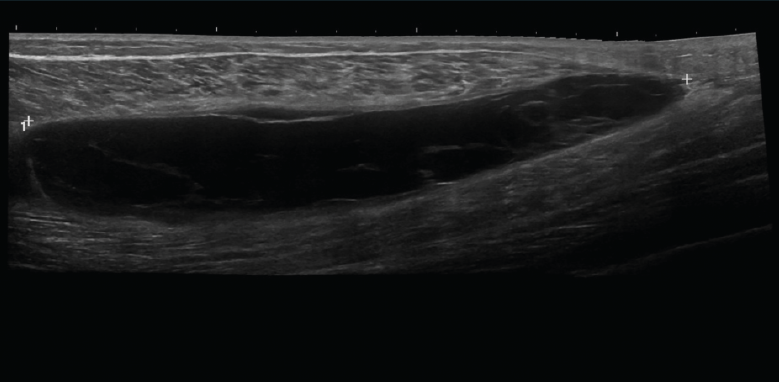

Figura 13. Corte sagital panorámico de una ecografía de la pierna con sonda lineal: gran rotura musculoaponeurótica entre el gemelo interno y el sóleo.

Se describen 4 grados de lesión muscular: grado 0, con ecografía negativa a pesar de tener clínica sugestiva; grado 1, con hiperecogenicidad en la lesión; y los grados 2 y 3, con regiones hipoecoicas por líquido adyacente a las fibras musculares. Cuando hay cicatrización, desaparece la región hipoecoica(8)(Figuras 11, 12, 13 y 14).

Se observan áreas hipoecoicas de solución de continuidad de las fibras tendinosas(7), con retracción de los márgenes con la contracción muscular cuando la rotura tendinosa es completa (Figuras 9 y 10).